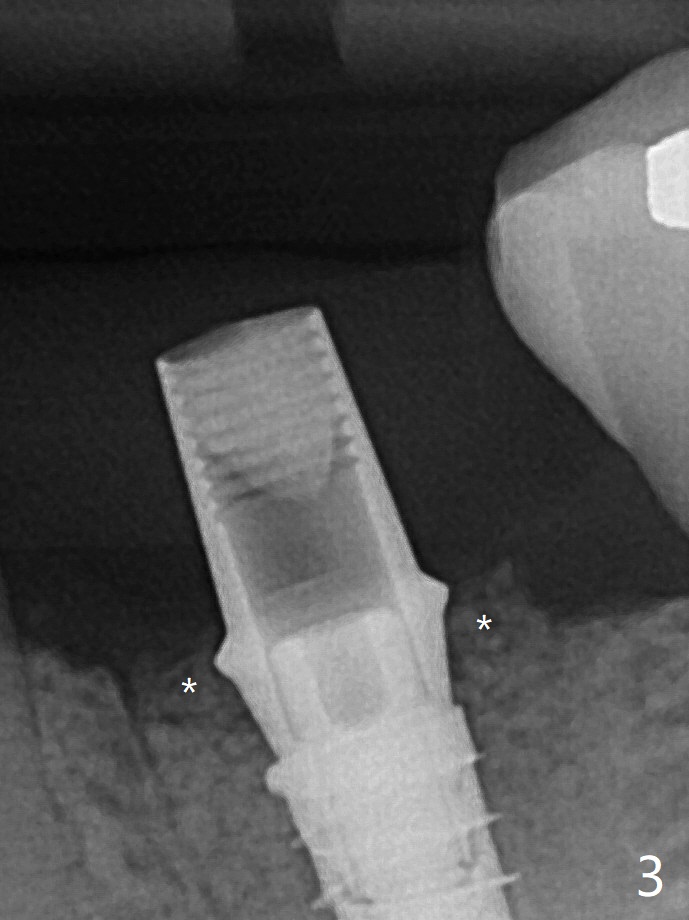

细短植体植入后基本保持在中隔之中(图二),扭力~30Ncm,在近中,远中剩余牙槽窝植骨后(图二:*),安置修复基台。制作临时牙冠后,在基台周围再次放置骨粉(图三)。